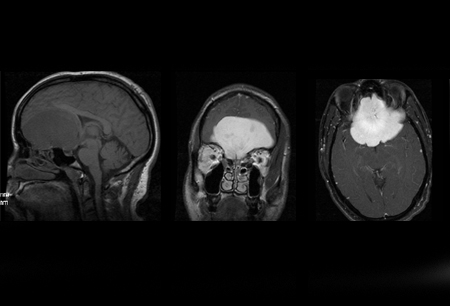

Meningioma

Imagem sagital (esquerda) demonstra grande massa extra-axial isointensa ao cérebro; o tumor capta avidamente o contraste administrado, como demonstrado na imagem coronal (centro da esquerda) e imagem axial (centro da direita). Observe o edema extenso circundante no tumor na imagem axial T2 (direita)

Da biblioteca pessoal do Dr. William T. Couldwell; usada com permissão